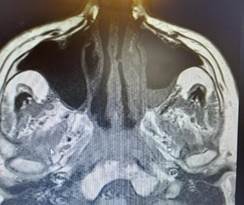

La resonancia magnética de senos paranasales mostró un engrosamiento mucoso con nivel hidroaéreo a nivel del seno maxilar izquierdo (Figura 2).

El paciente no se conocía diabético, debutó la enfermedad a los 65 años, fue tratado con hidratación parenteral, insulina regular con estabilización de la glicemia y recuperación del estado general. Por la protrusión ocular con parálisis del tercer par del ojo derecho se solicitó una resonancia magnética cerebral y de órbita, donde se observó un engrosamiento del nervio ocular derecho y de su vaina nerviosa y signos inflamatorios de la grasa adyacente. Estos cambios se extienden hasta casi alcanzar el quiasma óptico. También se observó una ocupación casi completa de la luz de las celdillas etmoidales posteriores, del seno esfenoidal. En los senos paranasales se observó un engrosamiento mucoso con nivel hidro-aéreo a nivel del seno maxilar izquierdo. Se inició antibióticos de amplio espectro por la sinusopatia. También al paciente se le realizó un tratamiento quirúrgico de la lesión retro orbitaria para diagnóstico y tratamiento, el examen directo de la lesión mostró hifas hialinas cenocíticas compatibles con mucorales, se inició anfotericina B que actualmente se encuentra recibiendo, con buena tolerancia.